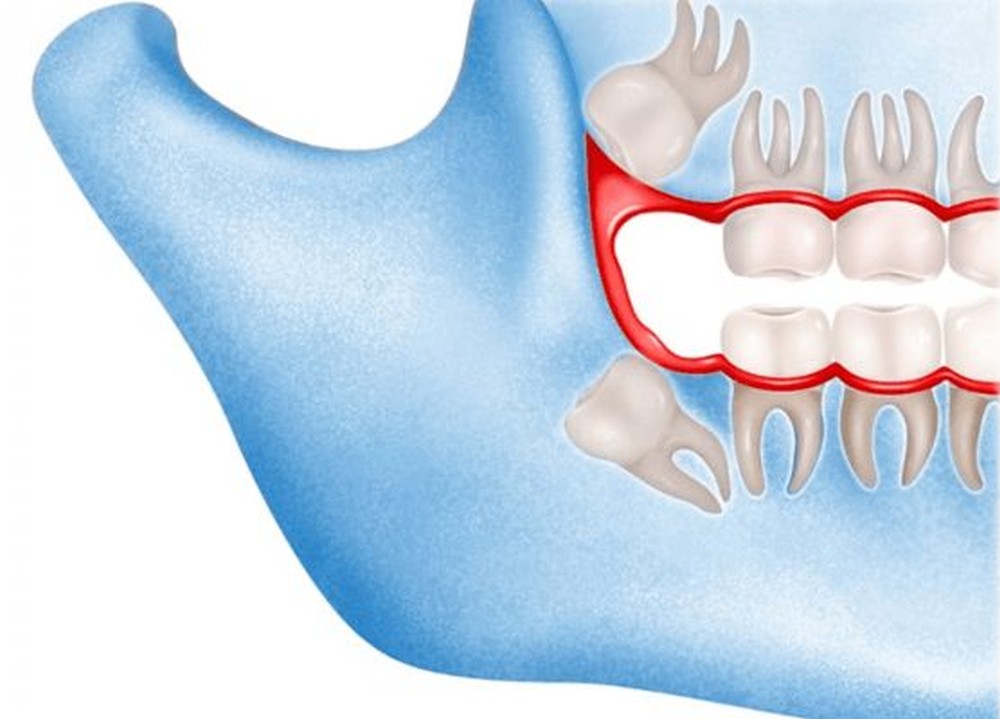

Sometimes, your wisdom teeth don’t come through properly, meaning they’re impacted. This can cause problems such as pain, swelling and infection. Having your wisdom teeth taken out can ease these symptoms.

They can get partially stuck in your gums or grow at an angle. This is called an impacted wisdom tooth. Even impacted wisdom teeth don’t always need to be taken out if they aren’t causing any symptoms.

Sometimes though, the way an impacted wisdom tooth is positioned can make it easy for food and bacteria to get trapped around the gum. This can lead to swollen and sore gums (pericoronitis), tooth decay and infection. If you’re having problems such as these, your dentist may recommend taking the impacted tooth out.